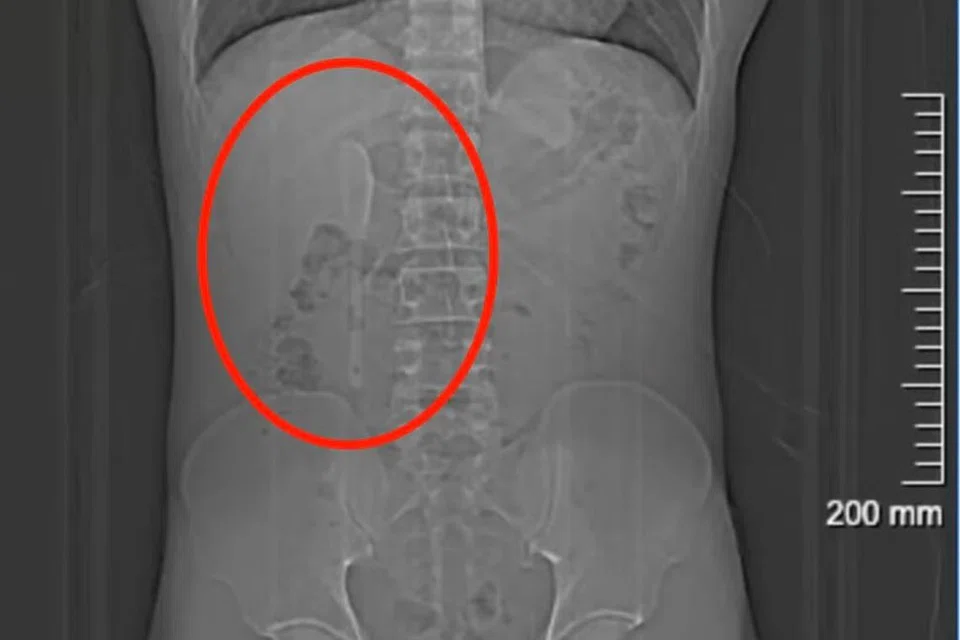

ஆனால், 15 சென்டிமீட்டர் நீளக் கரண்டி அவர் வயிற்றினுள் இருந்ததை அம்மருத்துவர் கண்டறிந்தார். அக்கரண்டி அவரது முன்சிறுகுடலில் ஆபத்தான நிலையில் சிக்கியிருந்தது. சிறு அசைவுகூட குடலைக் குத்திக் கிழித்து, ரத்தக்கசிவை ஏற்படுத்திவிடும் என்ற நிலை.

இந்நிலையில், யானின் வயிற்றில் சிக்கியிருந்த கரண்டியை வெளியில் எடுப்பது அவ்வளவு எளிதானதாக இல்லை என்று மருத்துவர்கள் கூறினர். ஜூன் 18ஆம் தேதி ஒன்றரை மணி நேர அறுவை சிகிச்சைமூலம் அது அகற்றப்பட்டது.